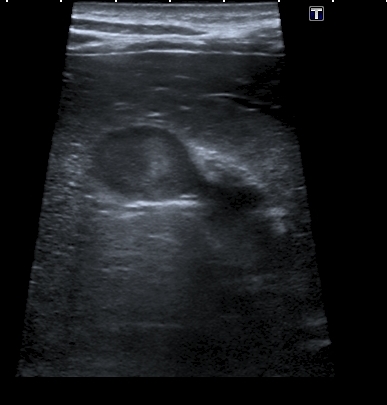

На УЗИ рядом с желчным пузырём определяется овоидное образование солидной струкутры с чёткими контурами.

При ЦДК кровоток в образовании не регистрировался, свободной жидкости в брюшной полости не было.

Была такая мысль, но очень уж разнится по структуре это образование от самого желчного пузыря. В динамичном изображении не было перехода полости желчного пузыря в образование. И чёткой стенки не было на всём протяжении...Dr Alex писал(а):Похоже на перегиб по типу "колпака", только он внизу а не сверху

Полазил в сети на предмет удвоения желчного пузыря. Ультразвуковая картина значительно зависит от уровня, степени удвоения и оттока желчи из удвоенной части желчевыводящей системы. Вероятно в моём случае могло быть фундальное удвоение или V - образный желчный пузырь с нарушением оттока из латеральной половины с общим пузырным протоком. Сосудистый рисунок в печени и её воротах изменён не был. В любом случае хирурги лечить его не собирались - клиники не было. Хотя описаны случаи камнеобразования и опухолей ( почему - то невином) в удвоенном ЖП.Инга писал(а):А что с протоками? Я так предполагаю, что должно быть тоже некое удвоение (р.s я не утверждаю, я предполагаю, я с удвоением ЖП не сталкивалась)